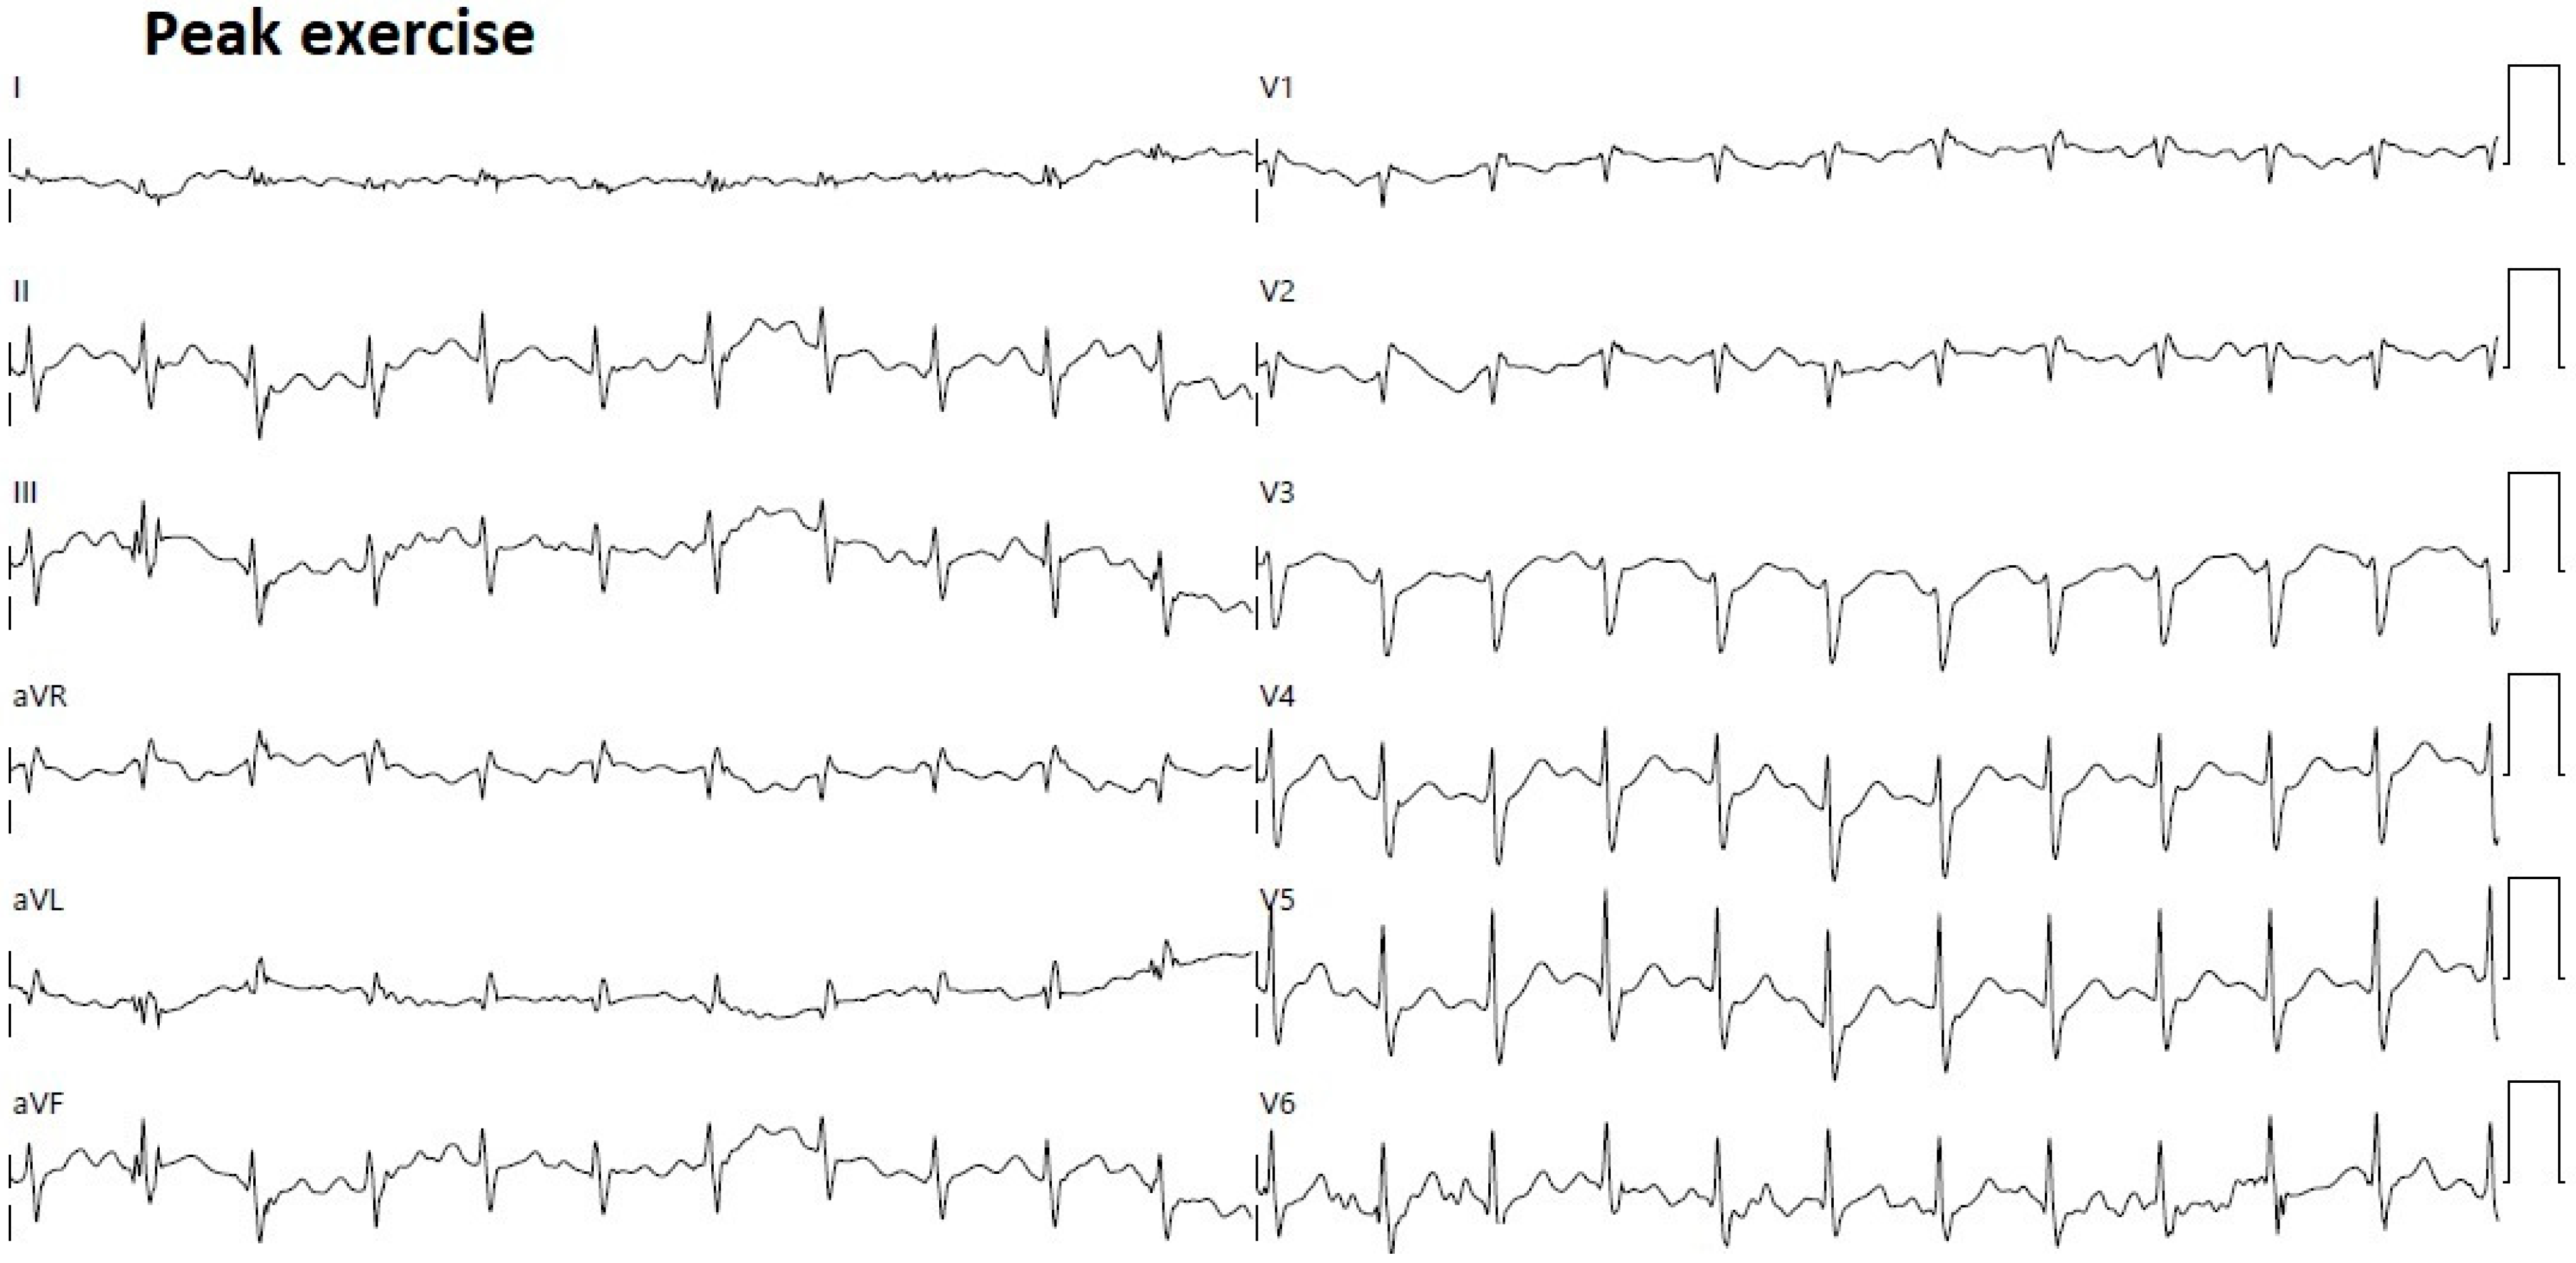

2. Clinical Case